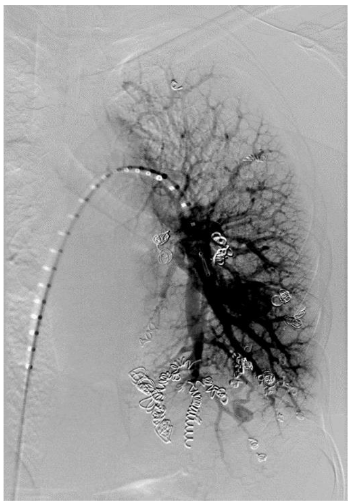

The patient is a 31-year-old gravida 4, para 2 who presented for routine obstetric care at 30 weeks gestation. She has a known history of HHT and PAVM, with prior embolization of two left-sided PAVMs. The patient was referred for evaluation of her pulmonary vascular status. At 30 weeks, the patient was noted to have a significant increase in the size of her PAVMs. The recommended imaging studies were significant for numerous bilateral PAVM and she underwent placement of 10 total vascular coils ante retrograde. Unfortunately, the largest PAVM measured 32mm and was located within the left lingula, where a feeding vessel could not be identified. The next largest PAVM measured 17 mm (located in the right upper lobe) and 23 mm (located in the right lower lobe), both of which were successfully treated.